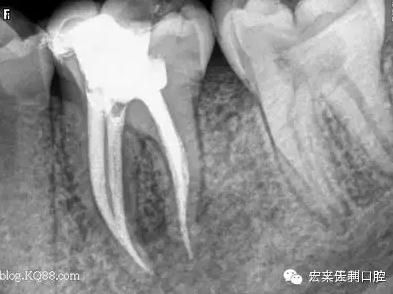

例如,我們有位女患者,在我們門(mén)診部根管治療結(jié)束后,建議她做個(gè)牙冠保護(hù)起來(lái),她當(dāng)時(shí)沒(méi)有聽(tīng)取意見(jiàn),過(guò)了三個(gè)月左右牙已劈裂。沒(méi)有任何辦法補(bǔ)救了,只能選擇拔掉一半,之前做的根管治療也前功盡棄。如圖:

1.jpg

2.jpg